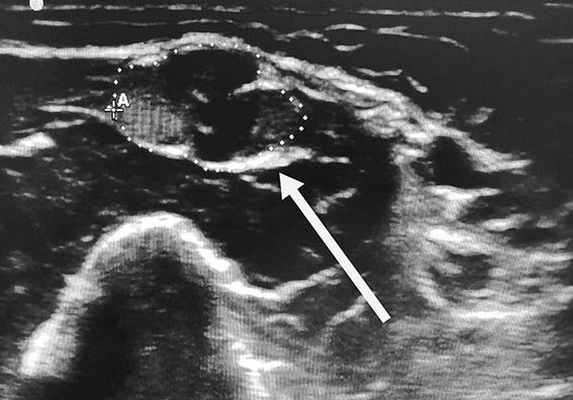

В канале кроме большеберцового нерва располагаются также сухожилия задней большеберцовой мышцы, длинного сгибателя пальцев и длинного сгибателя первого пальца. Большеберцовый нерв может подвергаться сдавлению на участке от внутренней лодыжки до среднего отдела стопы. В проксимальном отделе канала берет начало латеральный пяточный нерв. Дистальнее большеберцовый нерв разделяется на медиальный и латеральный подошвенные нервы. (Слева) Аксиальный срез, PD-ВИ: ганглионарная киста, оттесняющая большеберцовый нерв и задние большеберцовые сосуды медиально.

(Справа) Аксиальный срез, FS Т2-ВИ, этот же пациент: ганглионарная киста, оттесняющая большеберцовый нерв. (Слева) На аксиальном FS T1-ВИ с КУ у этого же пациента визуализируется объемное образование, характеризующееся однородным низким сигналом и не накапливающее контраст, что подтверждает его кистозную природу. Рядом с образованием видны контрастирующиеся сосуды. Также отмечается некоторое контрастное усиление отводящей мышцы первого пальца, связанное с ее денервацией.

(Справа) На данном фронтальном PD-ВИ видна ганглионарная киста, оттесняющая медиально заднюю большеберцовую артерию. (Слева) Сагиттальный срез, Т1-ВИ: ганглионарная киста канала предплюсны, расположенная рядом с задней большеберцовой веной.

(Справа) Сагиттальный срез, FS Т2-ВИ, этот же пациент: киста отличается однородным сигналом, ровными контурами и в некоторой степени дольчатым строением.